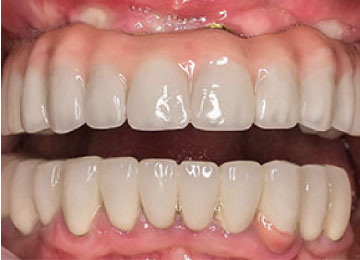

Имплантация зубов: фото "До" и "После"

Фото ДО

Фото ПОСЛЕ

Наведите для просмотра

All-on-4